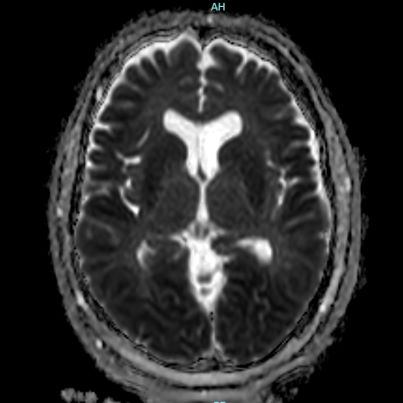

66 yaş, E

Kardiak arrest, 10 dk CPR öyküsü